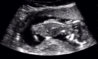

Nå har jeg visst i to dager at jeg var gravid og var litt nervøs for å ta ny test, men jeg ser jo nå veldig tydelig at det har veldig fint!